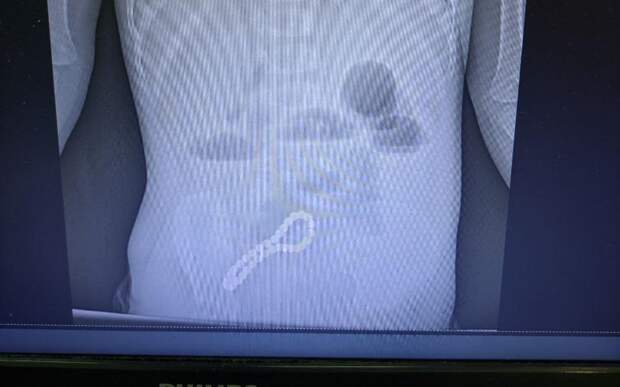

Маленький пациент поступил в ОДКБ с жалобами на нарушение работы желудочно-кишечного тракта. Рентгенограмма показала, что в кишечнике застряло инородной тело, которое нужно было срочно удалять.

Врачи решили оперировать. Проведена минилапаротомия — то есть через разрез передней брюшной стенки вытащили браслет.